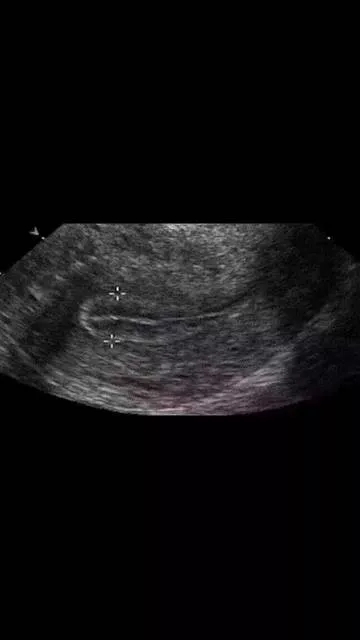

在平时进行内膜检测过程中,医生常会说到内膜太薄、太厚、不均质、有强光团,或内膜形态不好、三线不清、内膜线中断等等。

以上这些情况不利于胚胎着床和发育,不适宜移植新鲜胚胎,建议做一下宫腔镜检查,排除子宫内膜息肉、宫腔粘连、慢性子宫内膜炎症、内膜过度增生,以及双角子宫、单角子宫、子宫纵膈等等的病变,并进行相应的治疗。等内膜的病变去除,宫腔形态恢复以后再予以移植为好。